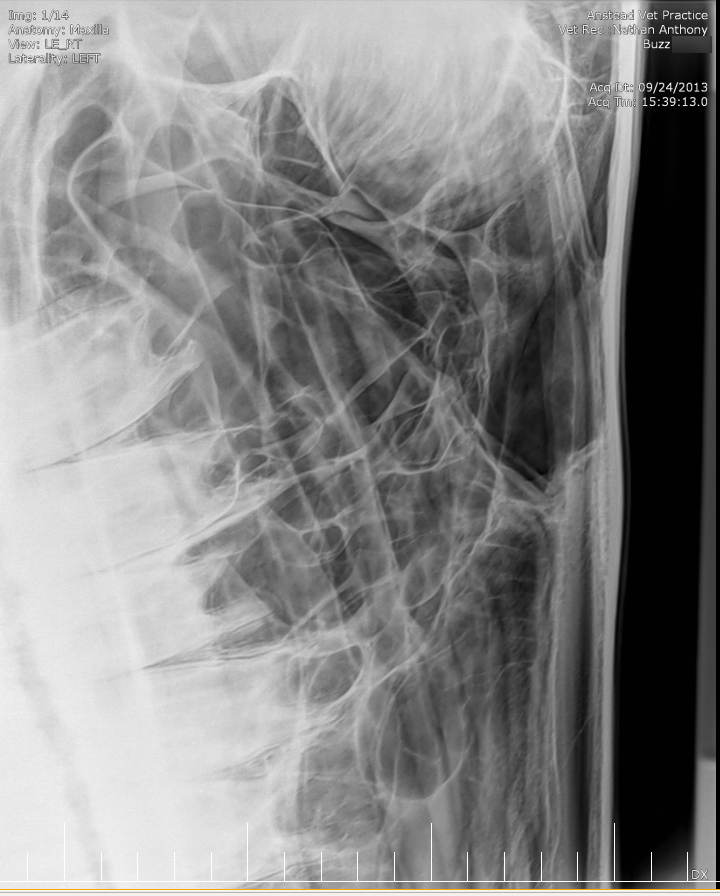

Posted on Sunday, May 8, 2016 - 6:24 pm: Thank you for the welcome!I did contact the lab to see if they still had the samples but they will only speak to the vets who submitted the samples. I've asked my vet to ask on my behalf but haven't yet heard back yet. The horse has been scoped and I was told that it all looked normal. The stylohoid bone and guttural pouches normal. The inflammation is mostly around the nostrils as per the pic but there are a couple of small spots further up inside the nose. He's also had his skull xrayed which I'm told also looked normal. I've included the pics at the bottom. I've included a list of other things here that have been tested to see if they influence the shaking or inflammation for the better or worse: - experimental course of Equity - Flixotide via inhaler - high dose of prednisolone - did work! - low dose of prednisolone - did not work - teeth checked by two different vet dentists - fly masks & nose nets - relocated him to several different places in the city incase it's an environmental allergen - all sorts of feed supplements - removed all hard feed, just feeding hay - stabled him 24/7 and fed him Haygain steamed hay incase it was something in the paddock - light/dark makes no difference to the shaking - it's not seasonal, happens year round I've also had bloodwork done and it showed a low red blood cell count. The blood was taken two weeks after the biopsies. My vet didn't think the low count was attributed to the blood loss from the biopsies so he suggested parasites but a worm count came back clean. I also had a test to see if there was blood in the manure, but nothing was found. There was no plan made to address the low RBC. Results are attached in a text file to maintain the spacing.

Xray images: